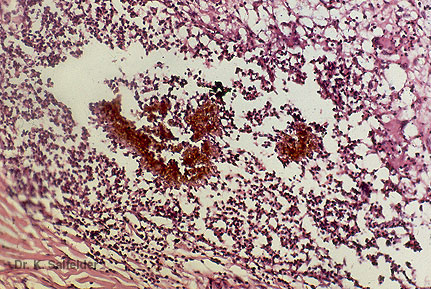

Abb. 16,36: Myzetome

Eumyzetom. Schwarze Druse derselben Pilzart wie in Abb. 16,36